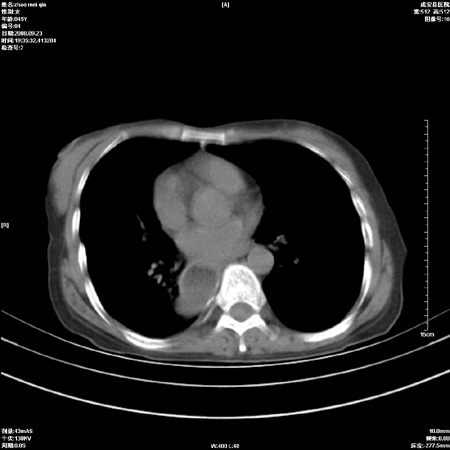

外伤后1小时 胸疼 是外伤后引起的吗?

食道扩张明显下端逐渐变窄,倒像贲门失迟缓

食道ca术后胸腔胃,右肺挫伤?

非外伤性改变,典型的贲门失迟缓症

食道扩张明显下端逐渐变窄,大量食物存留,象贲门失迟缓症。